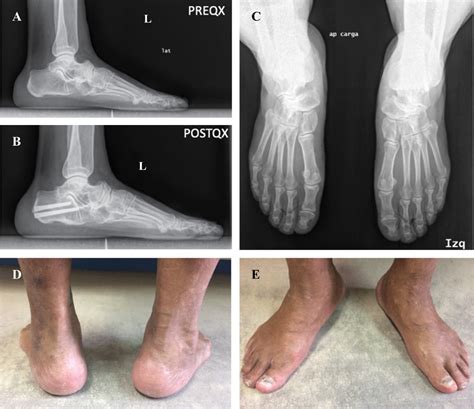

Typically, the syndrome affects adults between the ages of 40 and 60. Patients often present with persistent pain on the inner (medial) side of the foot, which gradually worsens with weight-bearing activities. As the navicular bone begins to collapse, the structural integrity of the foot’s arch is compromised, often leading to a secondary flatfoot deformity.

• Visible Deformity: A noticeable flattening of the arch or a bulging prominence in the midfoot area.

Treatment for Mueller Weiss Syndrome is generally staged based on the severity of the bone collapse and the level of pain the patient experiences. Physicians typically begin with conservative measures before considering invasive procedures.

When conservative treatments fail or when the deformity causes severe functional limitations, surgery may be necessary. Procedures are usually aimed at stabilizing the foot or addressing the resulting arthritic changes.

• Arthrodesis: The gold standard in advanced cases, where the affected joints are fused together to eliminate motion and provide long-term pain relief.